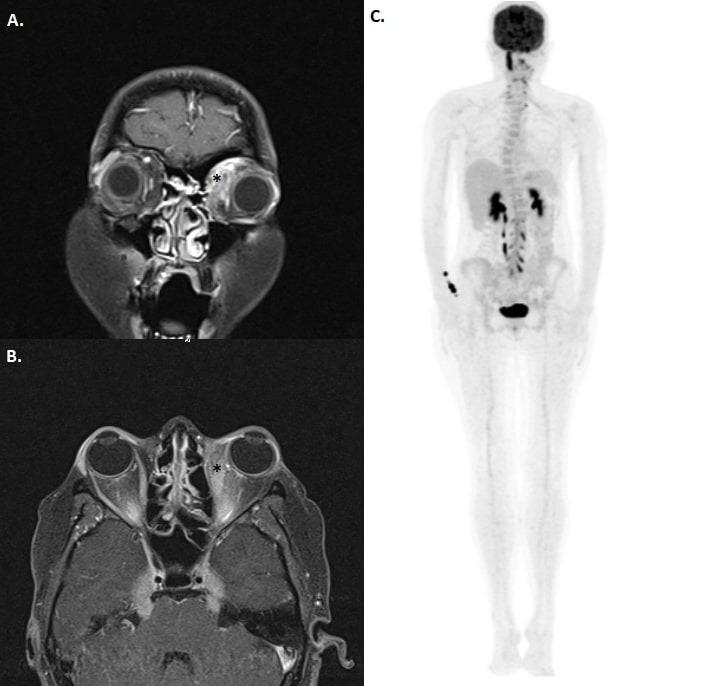

Case presentation: A 25-year-old woman presented first with preretinal infiltrates resembling uveitis and developed orbital and intracranial signs eventually during her evaluation. Clinical presentation worsened gradually. The patient developed bilateral proptosis, pupillary dilation and uvula deviation. Diagnostic orbital incision biopsy revealed T-cell lymphoproliferative disease.

Conclusion: This case gives evidence that intraocular involvement due to T-cell lymphoproliferative disease may present as a masquerade syndrome and should be kept in mind in patients with extraordinary presentation.